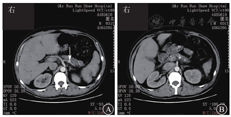

患者男,31岁,因"呕血伴黑便1个月余"于2017年11月24日入院。患者1个月余前劳累后出现恶心,后呕吐鲜血1次,量约50 mL,未就诊。数天后患者解成形黑便3次,每次量约100 g,伴头晕乏力,无黑矇晕厥。至浙江大学医学院附属邵逸夫医院急诊,查血常规示红细胞计数为2.35×1012/L,血红蛋白为34 g/L,平均红细胞体积为54.3 fL,平均血红蛋白水平263 g/L;血液生物化学检测示ALT为18 U/L,AST为14 U/L,ALP为91 U/L,GGT为63 U/L,TBil为19.6 mmol/L,DBil为8.2 mmol/L,LDH为265 U/L,淀粉酶为95 U/L,脂肪酶为82.22 U/L,胆碱脂酶为3 881 U/L,超敏CRP为0.6 mg/L。全腹增强CT检查示肝多发等低密度团片影,门静脉分支周围和胆囊稍水肿,脾部分陈旧梗死可能,脾静脉纤细并胃周侧支,脾动脉瘤(图1A),慢性胰腺炎(图1B),肝肾小囊肿,胃体后壁憩室。患者自述既往体格健康,有间断上腹隐痛,自认为"胃炎"未予诊治,平时未行健康体检。体格检查:体温为37.0 ℃,脉搏为96次/min,呼吸频率为19次/min,血压为129/72 mmHg(1 mmHg=0.133 kPa)。神志清楚,精神可,贫血貌,腹软,无压痛和反跳痛,肝脾肋下未及,肠鸣音6次/min,墨菲征阴性,移动性浊音阴性。

入院后予输注悬浮红细胞、抑酸护胃、补铁等治疗,患者未再出现呕血、黑便,大便隐血试验阴性。胃镜检查示十二指肠乳头处活动性渗血(图2)。腹部增强MRI检查示:①轻度肝硬化,轻度脂肪肝,动脉期肝脏异常强化灶,考虑异常灌注,左肝小囊肿。②脾大,脾部分梗死考虑,脾静脉显示不清,胃前方侧支形成;脾静脉与肠系膜上静脉汇合处血栓形成可能;脾动脉瘤。③考虑慢性胰腺炎。④胆囊底壁稍厚,胆囊腺肌症可能;右肾小囊肿。遂在介入科行脾动脉瘤栓塞术。术中见脾动脉局部囊袋样凸起,直径约8 mm,未见明显造影剂外溢,使用可控弹簧钢圈和栓塞胶进行栓塞(图3)。术后造影检查显示脾动脉主干及其远端分支显影良好,脾动脉瘤未见确切显示。患者术后多次复查血常规,血红蛋白水平维持在90 g/L以上。后复查胃镜示十二指肠乳头仍有活动性出血。遂行超声胃镜检查,内镜下见胃底、胃体上段多条曲张静脉,部分成团、成球样改变(图4A);十二指肠乳头结构无特殊,其开口可见墨绿色胆汁溢出;超声胃镜检查见胰腺实质回声不均匀,散在较密集点片状高回声区,呈云朵样;胰管显示,管壁回声增粗、增强;胆总管显示,胰头段胆管壁增厚;胰腺尾部见一3.0 cm×1.9 cm无回声区(图4B),部分囊壁呈片状增厚;脾脏显示增厚。诊断:慢性胰腺炎;胰尾部囊性病变,性质待定;重度胃底静脉曲张。对症支持治疗后患者未再解黑便,复查血红蛋白水平稳定,患者拒绝进一步检查,要求出院随访。